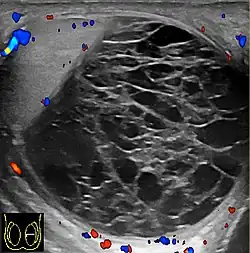

Doppler ultrasound of epididymitis, seen as a substantial increase in blood flow in the left epididymis (top image), while it is normal in the right (bottom image). The thickness of the epididymis (between yellow crosses) is only slightly increased (7 mm).

Doppler ultrasound of the scrotum of the same case, in the axial plane, showing orchitis (as part of epididymo-orchitis) as hypoechogenic and slightly heterogenic left testicular tissue (right in image), with an increased blood flow. There is also swelling of peritesticular tissue.